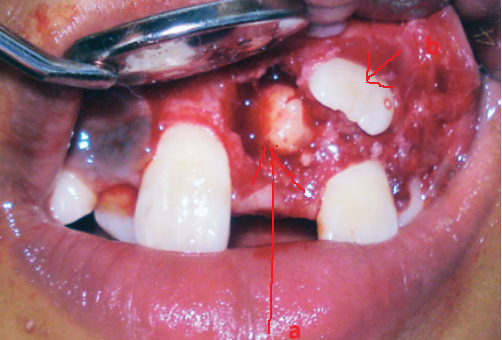

Răng thừa làm cho R21 mọc thưa và lệch về phía môi Răng thừa (a) làm R11 (b) bị kẹt không mọc ra được

Răng thừa gây nang xương hàm trên Răng thừa mọc vào tiền đình mũi

Hình 2: Một số biến chứng của răng thừa